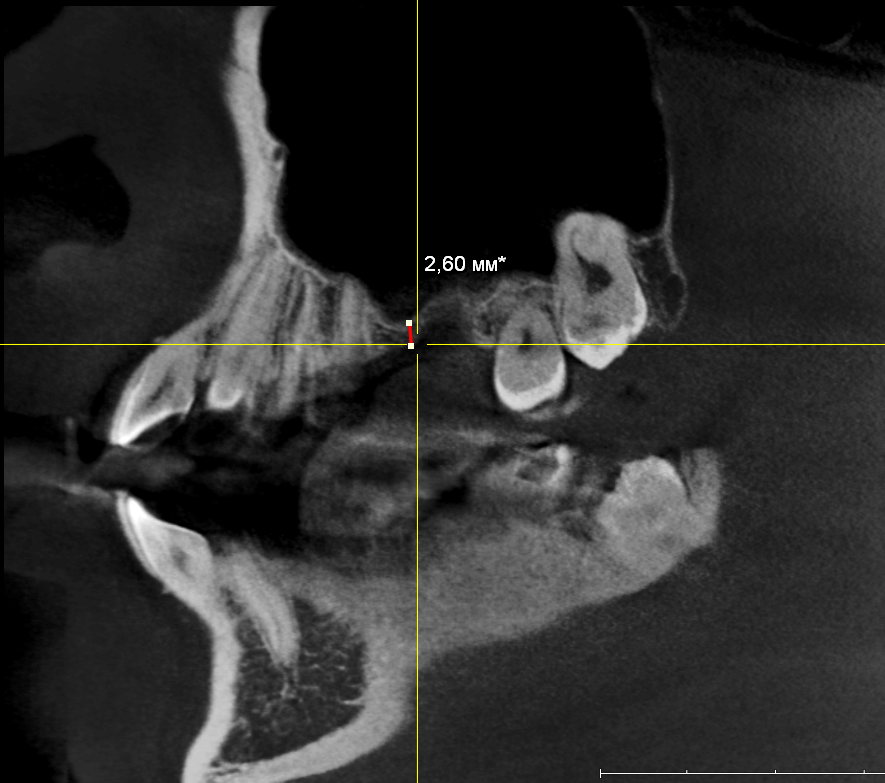

Пациенту удалили 26 зуб около двух месяцев назад. Вот компьютерная томография

Подробнее:

В общем, тут нужен синуслифтинг. И, исходя из последних данных об этой операции, 2,6 мм до дна верхнечелюстной полости достаточно, чтобы нормально стабилизировать имплантат, в т. ч. Astra Tech.

26 зуб удалён относительно недавно, поэтому альвеолярный гребень сохранил ширину — это даст нам возможность поставить бескомпромиссно большой по диаметру имплантат — 5.0 мм.

В этой конкретной клинической ситуации первичная стабильность не зависит от длины имплантата, поэтому длину можно выбирать любую. Мы возьмём оптимальную — 9.0 мм. Ибо проще будет с синуслифтингом.